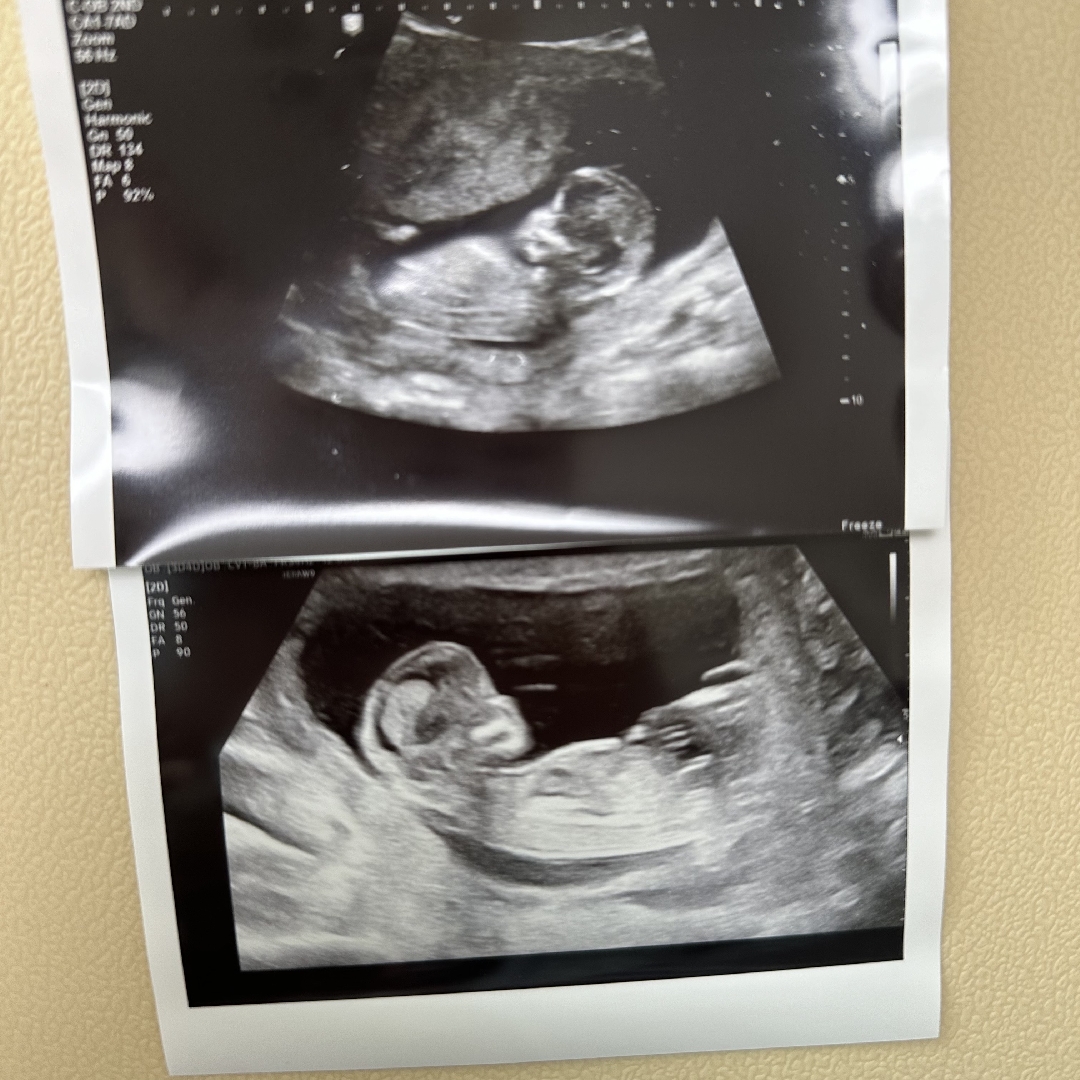

각도법 고수님들~~ 우리 욤욤이좀 봐주세요!

장인어른이랑 아들인지 딸인지 내기했는데 고수님들 봐주세요!!!ㅎㅎㅎㅎ

딸?!